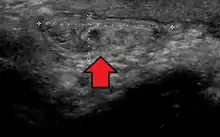

Ultrasound showing an inguinal hernia

An incarcerated inguinal hernia as seen on CT

By far the most common hernias (up to 75% of all abdominal hernias) are inguinal hernias, which are further divided into the more common indirect inguinal hernia (2/3, depicted here), in which the inguinal canal is entered via a congenital weakness at its entrance (the internal inguinal ring), and the direct inguinal hernia type (1/3), where the hernia contents push through a weak spot in the back wall of the inguinal canal. An indirect inguinal hernia and a direct inguinal hernia can be distinguished by their positioning in relation to the inferior epigastric vessels. An indirect hernia is situated laterally to these vessels, whereas a direct hernia is positioned medially to them. Inguinal hernias are the most common type of hernia in both men and women. In some selected cases, they may require surgery.